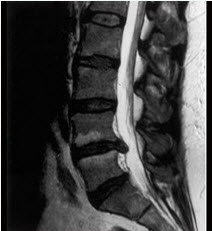

如图,硬膜外间隙哪项不对()

A、是一充满脂肪.血管和淋巴管的潜在间隙

B、在腰处最宽约5~6mm

C、在中胸部宽约3~5mm

D、在下颈部宽约1.5~2mm

E、上自枕骨大孔,下至骶2

E